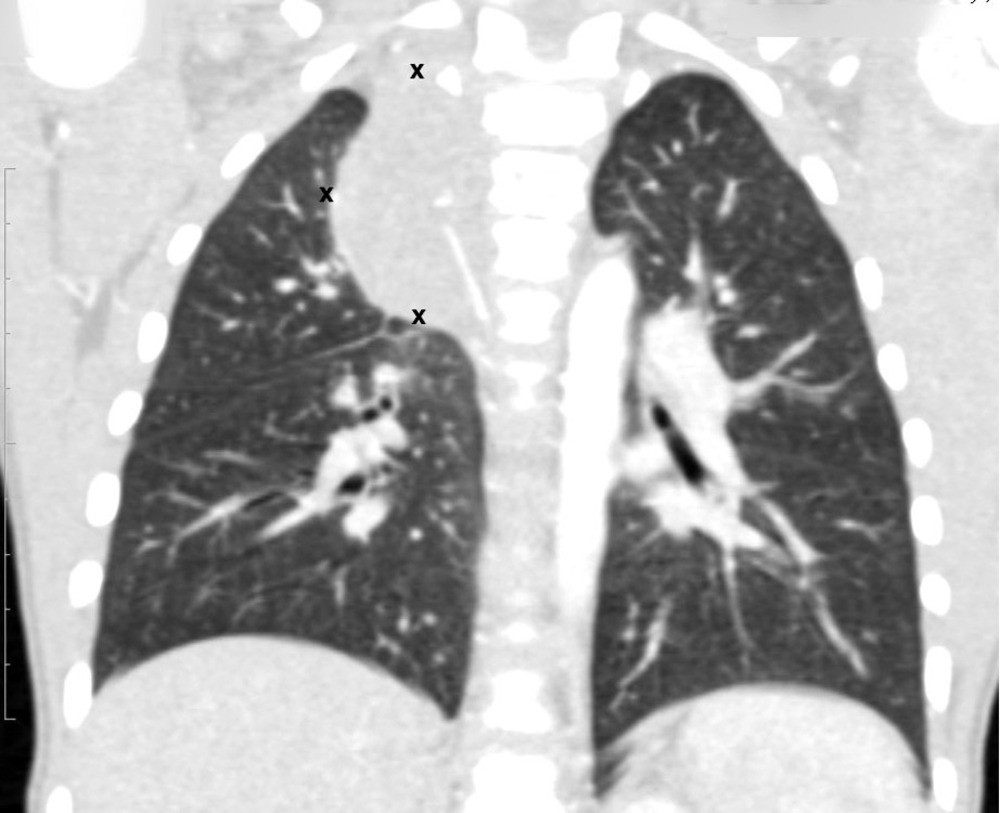

Средостение

В средостении в большинстве случаев присутствуют крупные опухоли, но при этом синдром сдавления верхней полой вены диагностируется редко.

Risunok6.jpgРисунок 6. - КТ органов грудной клетки – семинома средостения.

Гистологическая картина новообразования в основном смешанного происхождения, имеет тератоидный компонент и клетки, которые характерны для новообразования желточного мешка.